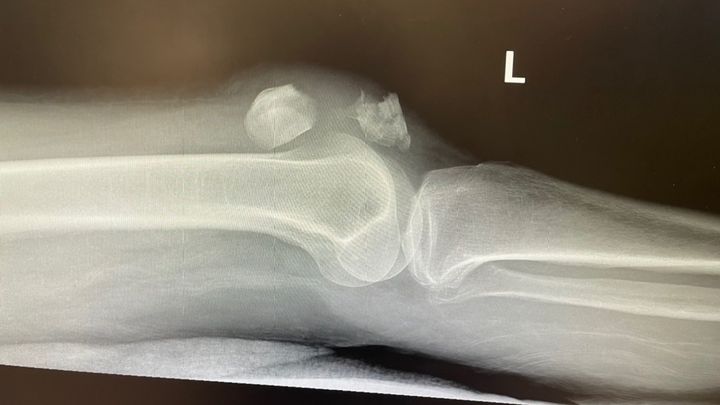

Funds for Medical and rehab expenses including funds for day to day expenses in SanDiego